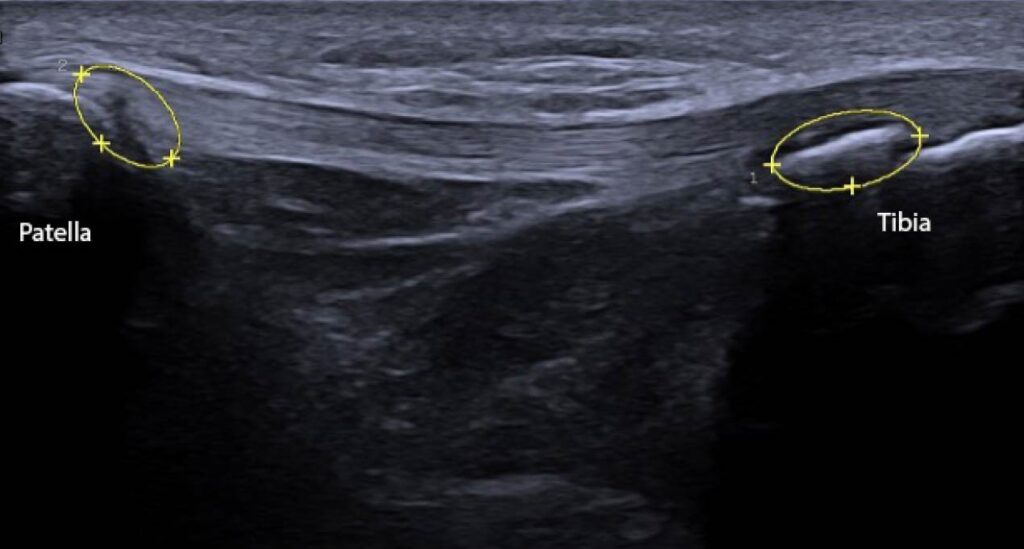

Figure 1: Ultrasound image (ACUSON Redwood Ultrasound System, Siemens Medical Solutions USA, Inc., Issaquah, WA) of the patellar tendon with 2 observable deformities. On the right, there is a bony deformity at the distal end of the patellar tendon at the tibial tuberosity. On the left, there is a darkened spot on the patellar tendon at the inferior pole of the patella, indicating inflammation with potential disruption to the patellar tendon.

Basic measurements that can be obtained with DU include tendon length, width, and thickness. Tendon length and width primarily provide more information regarding the basic structure of the patellar tendon, with the potential of observing obvious tendon abnormalities (Figure 1). Some abnormalities may include increased or decreased tendon length due to limb length or subject height.10 Other deformities that may be observed when measuring tendon length and width are obvious tears or partial tears in the tendon, but those abnormalities may require further evaluation via MRI.